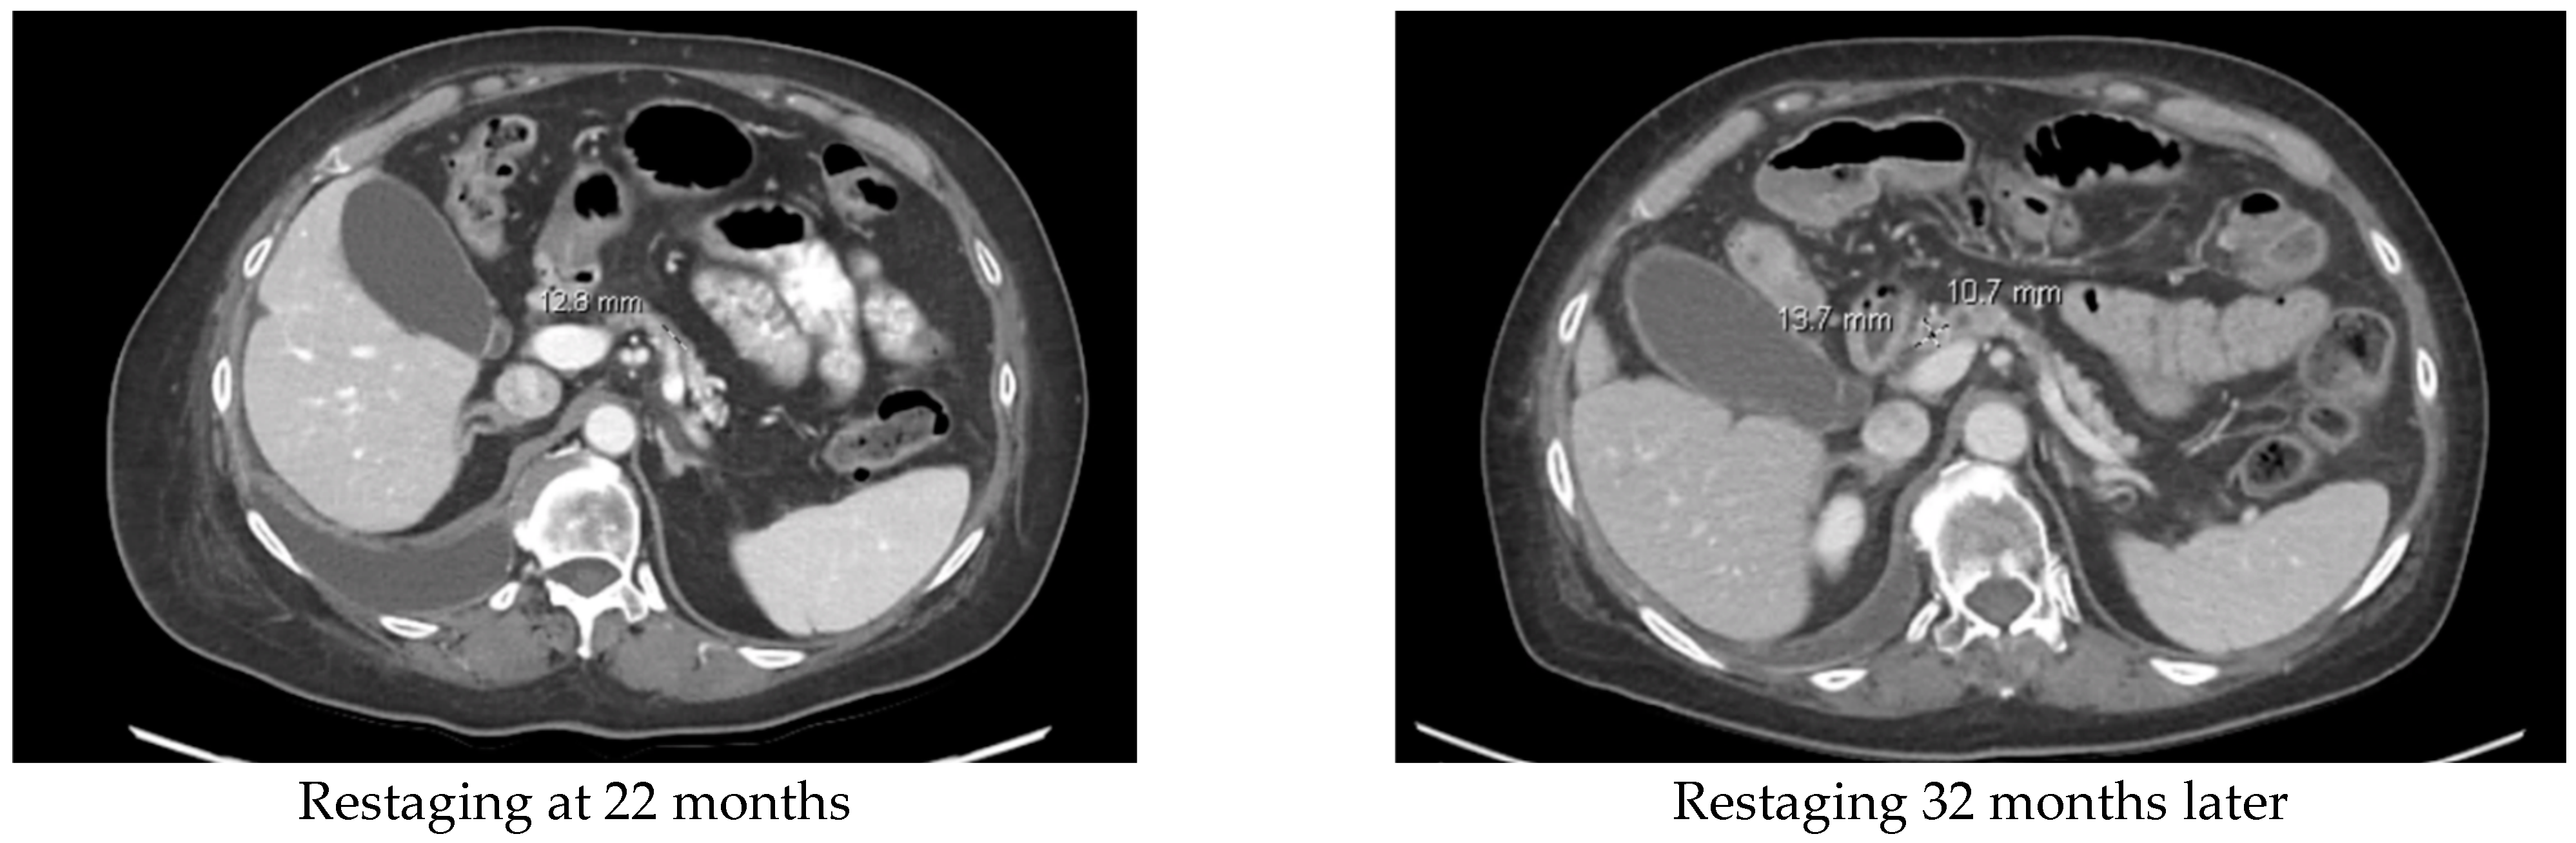

| 58/F | Folfirinox 1 mo switch when RET-1 gene fusion identified. | Selpercatinib. Continuing to show PR. | 26 | |